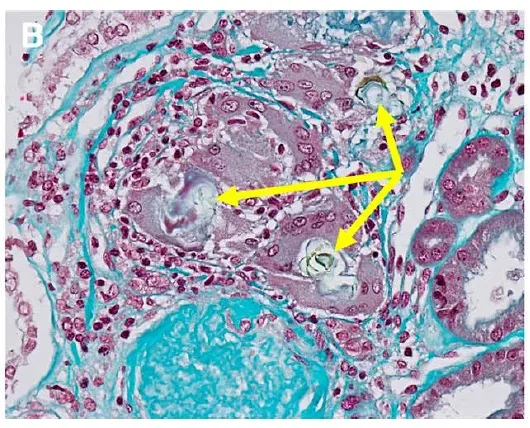

Idoso com GNRP, qual seria sua principal hipótese diagnóstica?

Idoso com GNRP, qual seria sua principal hipótese diagnóstica?Caso típico de GNRP em paciente idosos. Vendo a imagem, qual seria sua primeira hipótese diagnóstica?